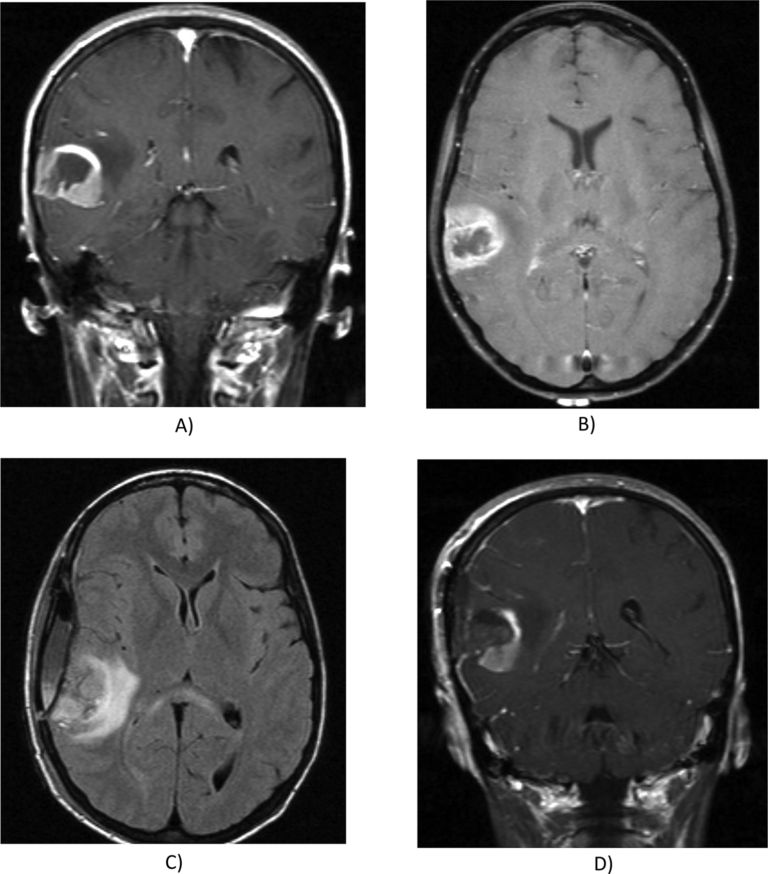

To develop and externally validate ultrasound nomograms combining BI-RADS features and quantitative morphometric characteristics, and to compare their performance with expert radiologists and large language models in biopsy recommendation and malignancy prediction for breast lesions…